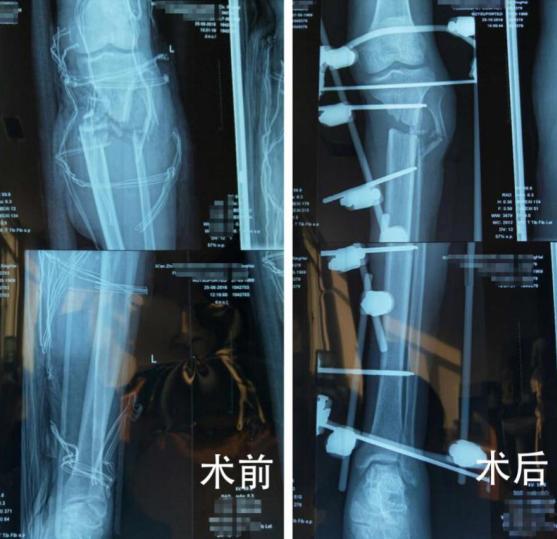

入院时,患者由于出血非常量多,也处于创伤性失血性休克状态,远端肢体苍白无血运,断肢创面泥沙污染严重,伤情十分危急。 综合创伤一病区张亮主任紧急组织术前病案会诊、评估患者伤情:“患者左小腿自膝关节以远10cm处离断,肢体断面参差不齐,骨、肌肉、血管、神经组织外露、污染严重,因此离断肢体再植时间紧迫、难度极大。”

伤情复杂,刻不容缓!“在纠正生命体征的同时,进行保肢。同时,保肢手术难度在于血管的吻合、骨、神经肌腱的修复,需要高超的显微外科技术才能完成修复工作。”危急时刻,创伤外科一病区科室团队最终决定:快速输血、输液,纠正失血性休克,在生命各项体征基本稳定前提下,为患者进行保肢手术,以尽最大可能保住肢体。张亮主任一边安排患者进行必要的术前检查,紧急与麻醉科联系,立即展开手术。术中,行彻底清创、骨折复位外架固定,血管、神经、肌肉探查修复,经9小时紧急抢救,手术顺利完成。

“患者在一期手术治疗后,由于外伤导致左胫骨部分骨质缺损而致小腿肢体短缩约5cm。肢体的短缩将严重影响下肢功能,在再植肢体伤口愈合后,医生们又将患者即时进行再植肢体得骨延长术,经过6个月连续有序的科学治理,再植肢体功能恢复非常好。如今已能扶拐自行行走,患者及家属都非常满意。“肢体保住了,还可以负重行走,真得已经超出我的预期了!太感谢你们了!”患者杜师傅激动万分。